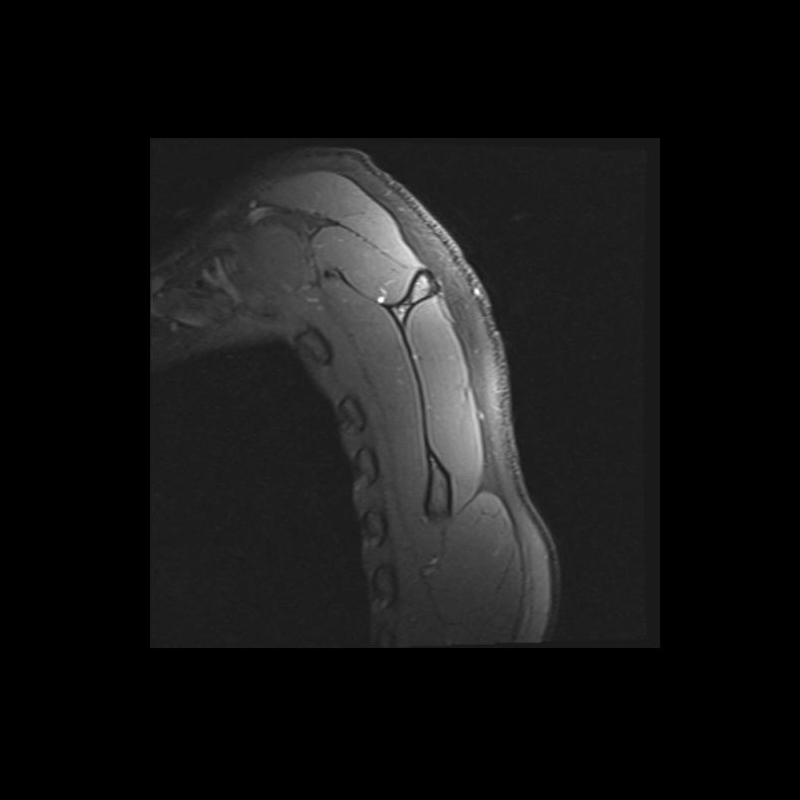

Shoulder MRI Anatomy